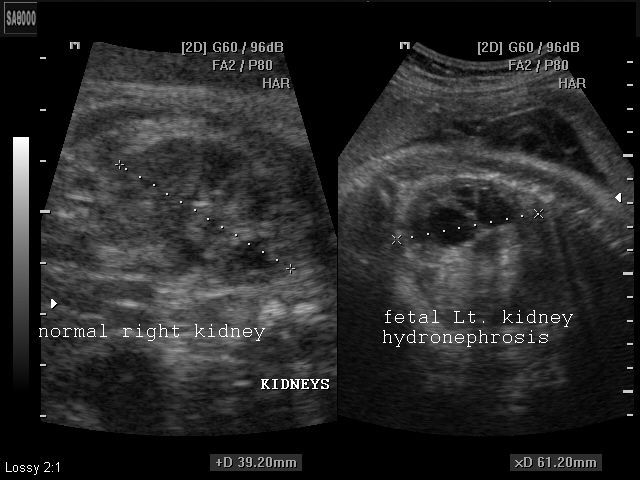

These ultrasound images reveal unilateral hydronephrosis of the left fetal kidney. The renal pelvis and calyces appear dilated with thinning of the renal parenchyma in the affected kidney. The commonest cause of such hydronephrosis is PUJ (Pelvi-ureteral junctional) obstruction, usually functional. The left ureter does not appear to be dilated. For cases of dilatation of the renal pelvis, it is labelled as abnormal if the RPD (renal pelvic A-P diameter) is more than 10mm (after 20 weeks gestational age). If less than 20 weeks, more than 4mm. is abnormal. These ultrasound images are courtesy of Dr. Arun Mahajan, Delhi, India.